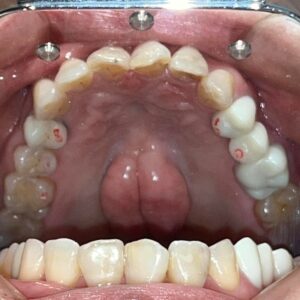

元々、上の前歯に入っている補綴物の状態がこちらです。

歯と歯茎の境が黒くなっているのがわかります。

まずは元々入っている補綴物を外し、仮の歯を入れていきます。

仮歯を入れた状態がこちらです。

そして前歯にフルジルコニアセラミッククラウンを入れた状態がこちらです。

Before After

歯と歯茎の境もなくしっかりとフィットし、綺麗な仕上がりになりました。

笑顔もとても素敵ですね♪